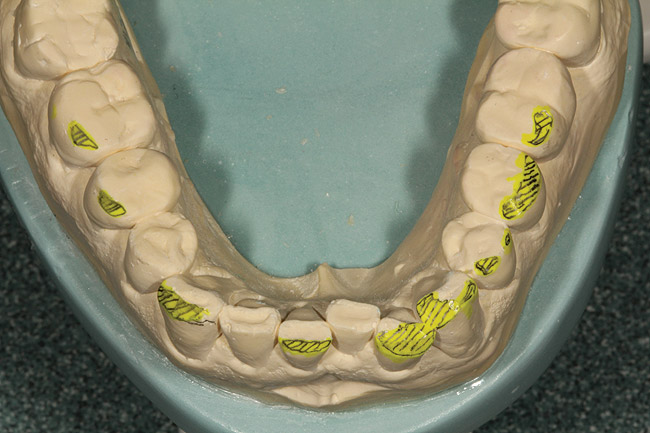

Figure 12  View of the reduction preformed on the upper preoperative model.

Figure 12

After highlighting these reductions on the preoperative model (Figure 12), wax was then added to both form and function (Figure 13 through Figure 15). This additive-reductive model operated as the essential blueprint for the provisional and ultimately the definitive restorations.